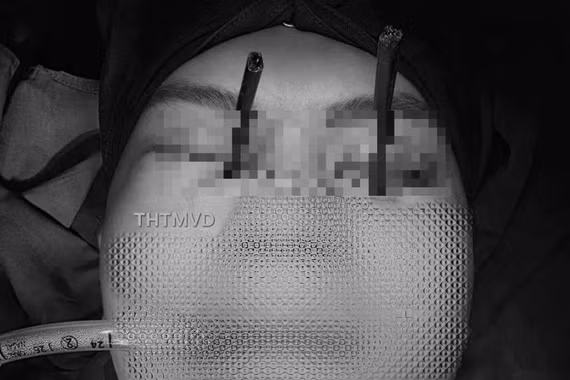

di-vat-3.png

Nội soi xác định xương gà đã găm vào niêm mạc, tạo vết rách nhỏ - Ảnh BVCC